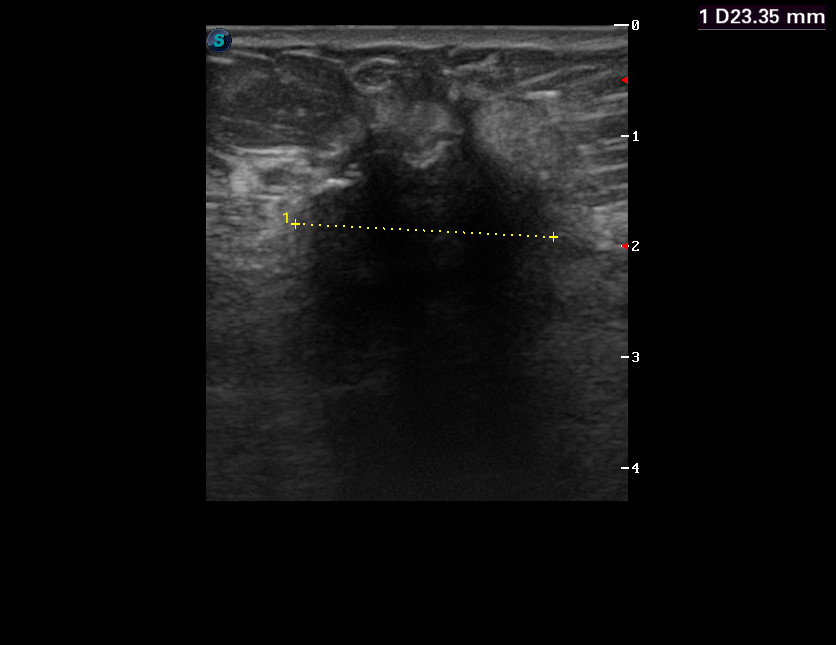

Бабушка 1936 г, правый сосок втянут

Похоже что есть?

А что там в подмышечной впадине? Но очень похоже... и должно определяться пальпаторно,судя по размерам.

zubr писал(а):А что там в подмышечной впадине? Но очень похоже... и должно определяться пальпаторно,судя по размерам.

Да, пальпаторно есть.

Бабушку отправили к онкологам.